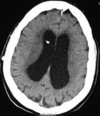

**IVH** - On CT imaging it appears as hyperdensity within the dark CSF spaces within the ventricles.

Hydrocephalus: ventriculomegaly with compression of the brain parenchyma

**Intraventricular haemorrhage**: hyperintense (bright) blood within the ventricles (with a fluid level); may be **primary**: started in ventricles or **secondary**: extension of extra-ventricular bleed (usually SAH or intracerebral e.g. basal ganglia)